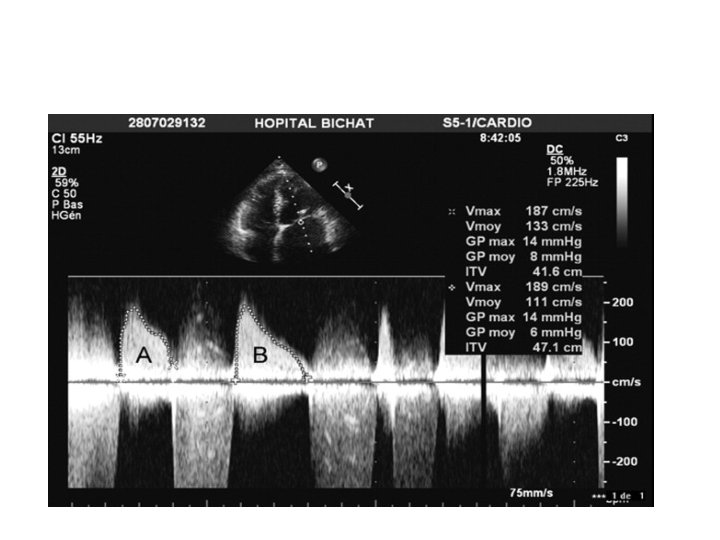

Pressure gradient • Maximal & mean gradient are calculated. • Mean gradient is relevant hemodynamic finding. • Maximal gradient is derived from peak mitral velocity, which is influenced by left atrial compliance & LV diastolic function. • In AF : Avg of 5 cycles with least variation of R-R interval. • HR at which gradients are obtained to be noted.

Pressure gradient • Not the best marker of severity of MS. • Depend on heart rate, cardiac output(CO) & associated MR. • Tachycardia, increased CO & associated MR overestimates gradient.

Pressure Gradients varies with HR HR=72 HR=100